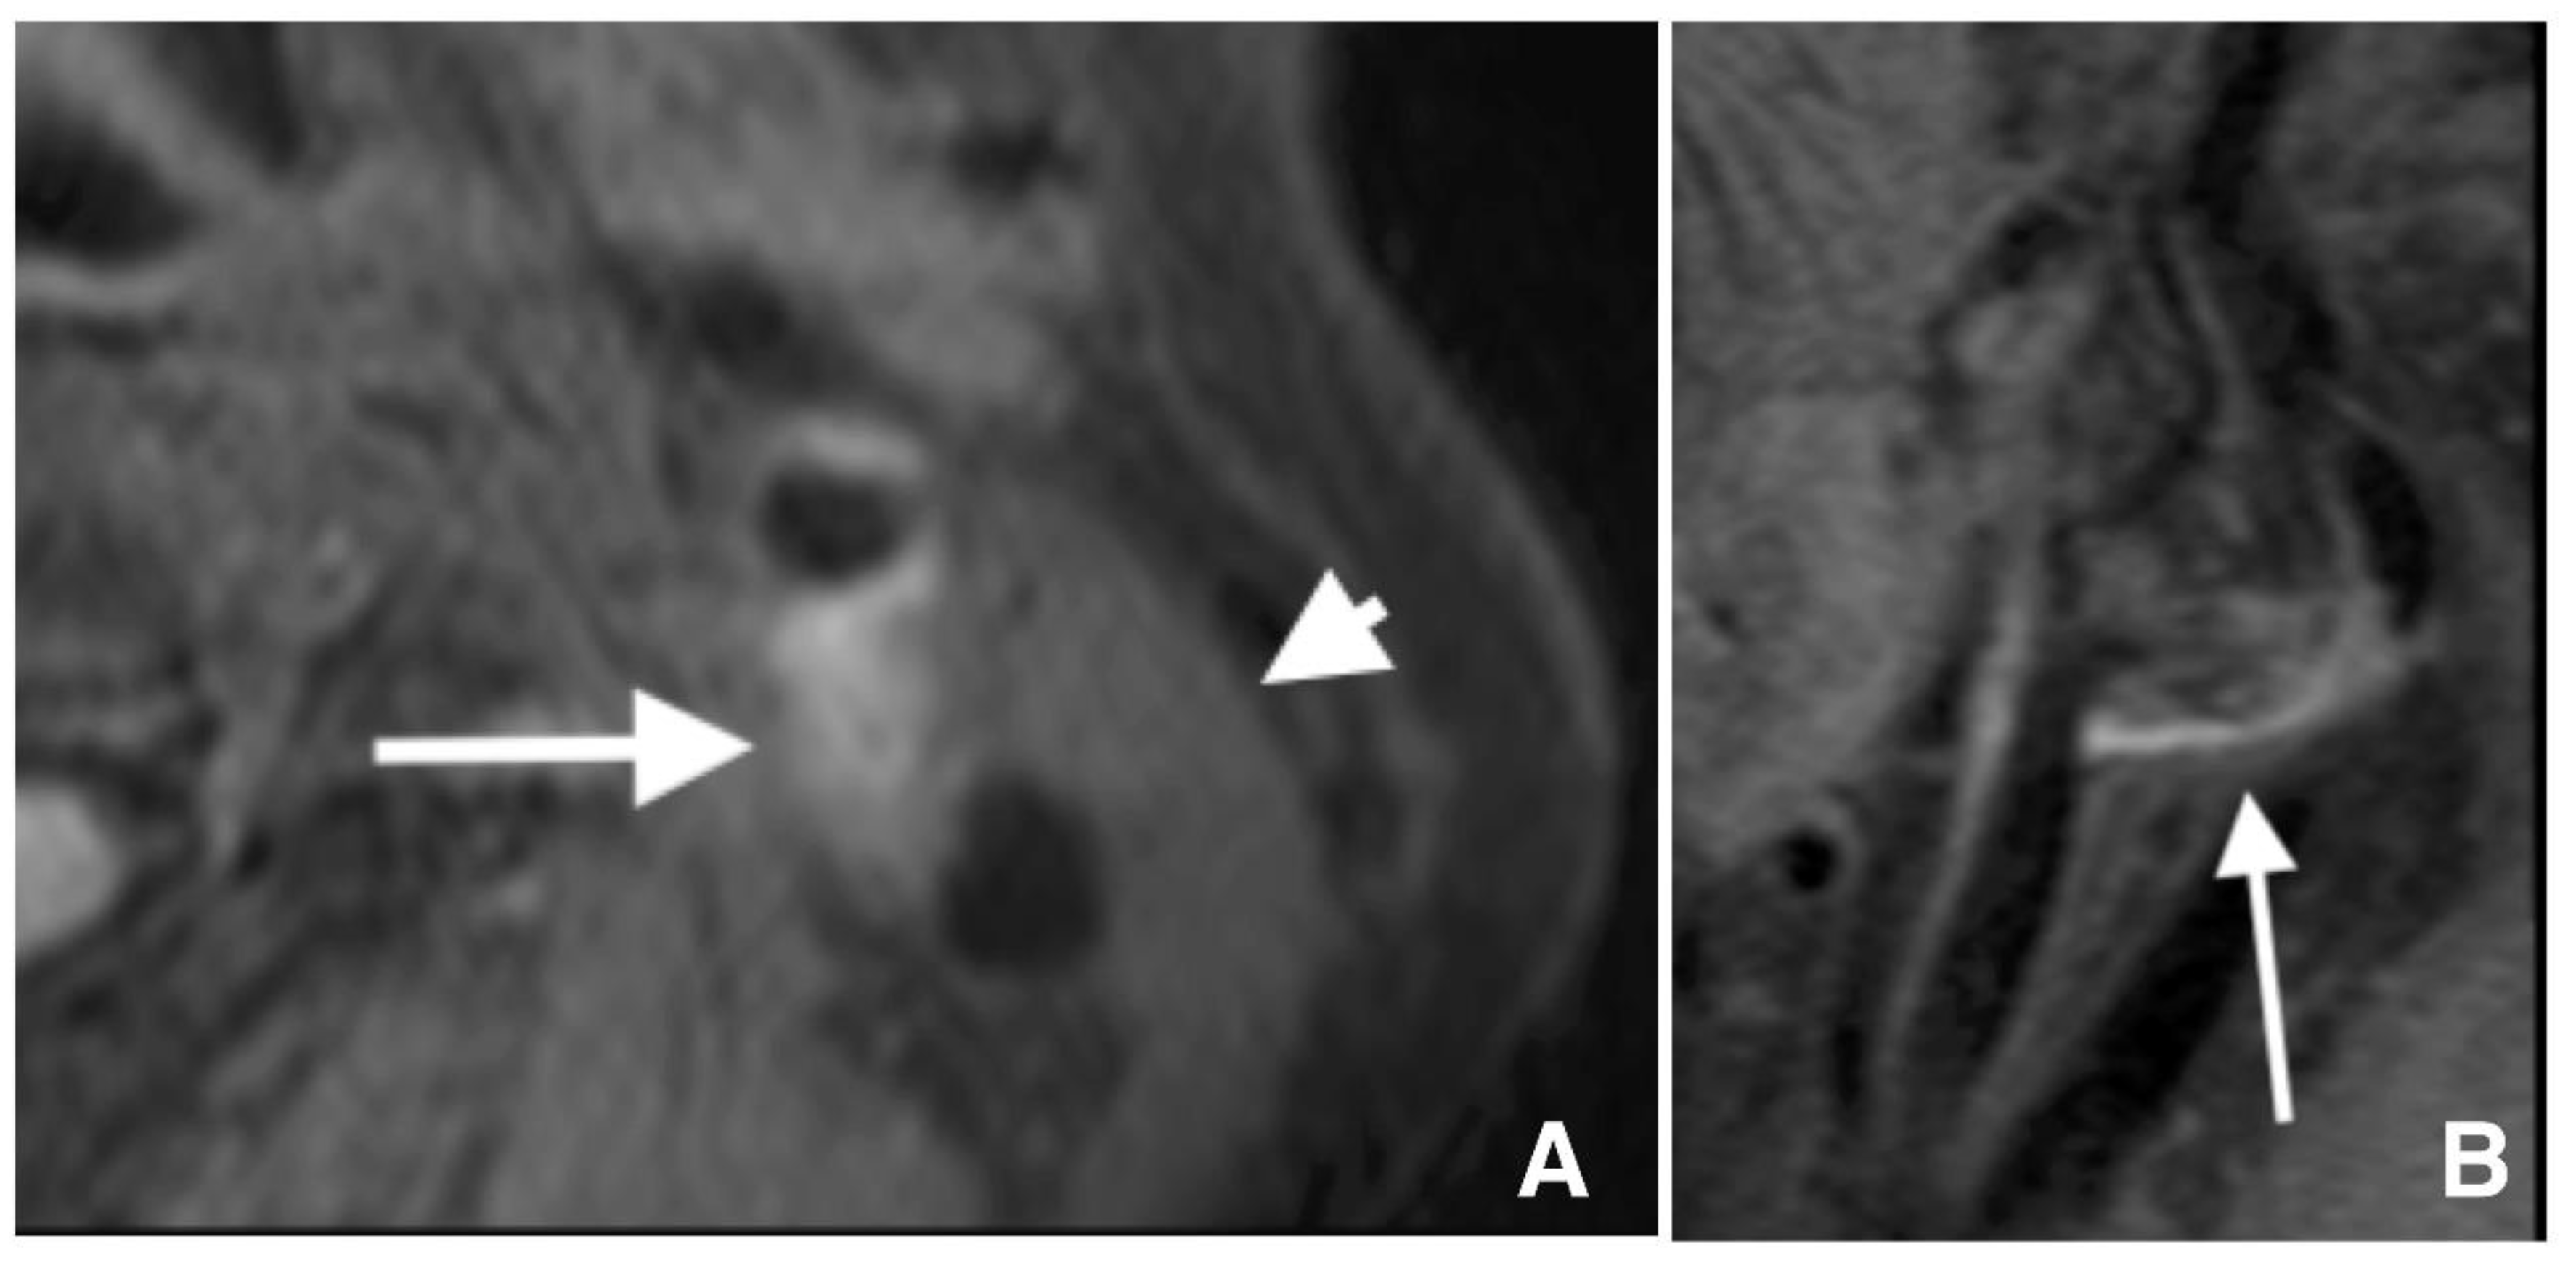

2.2. Carotid Artery Plaque Imaging

2.3. Definition of Lesions with IPH